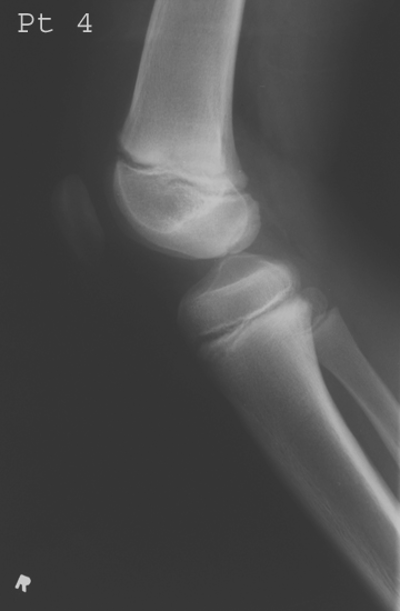

Most common site of Osteochondritis Dissecans?

Medial femoral condyle (75%).

How is it diagnosed radiographically?

MRI/CT for cartilage lesions; X-ray shows fragments and site of origin; tunnel view for knee.

What stage is this disease at?

Stage 4